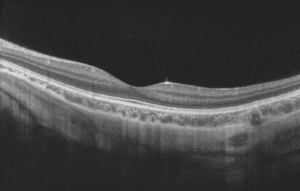

OCT left hand side

OCT right hand side